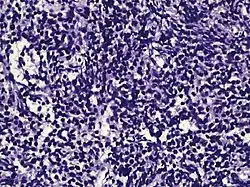

| Small-cell carcinoma | 0.3–2%[14][15][notes 1] | |

Half of cases have usual acinar components[1] | ||||